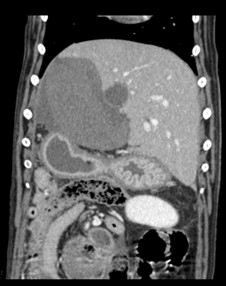

CT image showing a normal looking liver on the right compared to the abnormal side towards the left of the picture.

A CT scan at the Wiltshire small animal hospital, which recently earned six outstanding PSS awards, revealed Riley was suffering from two liver lobe torsions (LLT), an extremely rare complaint in animals and especially in dogs.

“Riley was stabilised at Eastcott with the help of our anaesthesia team and underwent a CT scan. We the assistance of our imager on duty, we diagnosed Riley with torsion of two of his liver lobes.